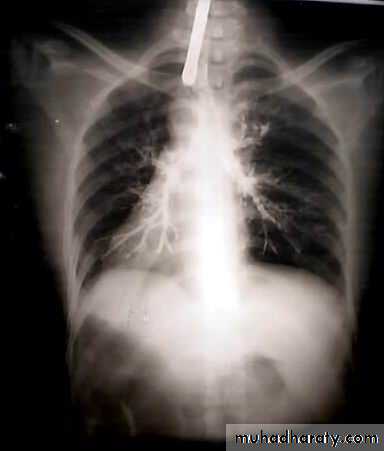

• A-Asymptomatic• Any smooth homogenous opacity of uniform density with clear cut border and little or no reaction around it on a chest X-Ray is a hydatid cyst unless proved the other wise .

• Radiological Findings

• 1-Smooth homogenous opacity (Intact H.C).• 2-Partial rupture (per vesicular pneumocyst).

• 3-Complete rupture (Water –lilly sign) .

• 4-Formation of lung abscess(Air –fluid level) .

• 5-Completely coughed out cyst(empty cavity )

• 6-Rupture into the pleura (hydropneumothorax)